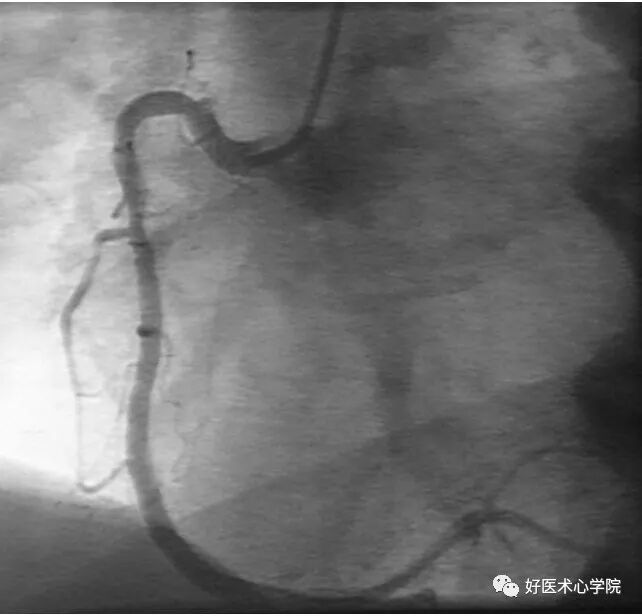

9. 侧支循环(Collateral Circulation)

当冠状动脉严重狭窄或阻塞时,近端灌注压明显下降,刺激侧支循环形成,血管远端被侧支循环逆向供血而显影。

造影导丝是什么珍藏 冠脉造影从流程到诊断,基础必备!_https://www.jmylbn.com_新闻资讯_第96张

侧枝:右冠脉→左前降支